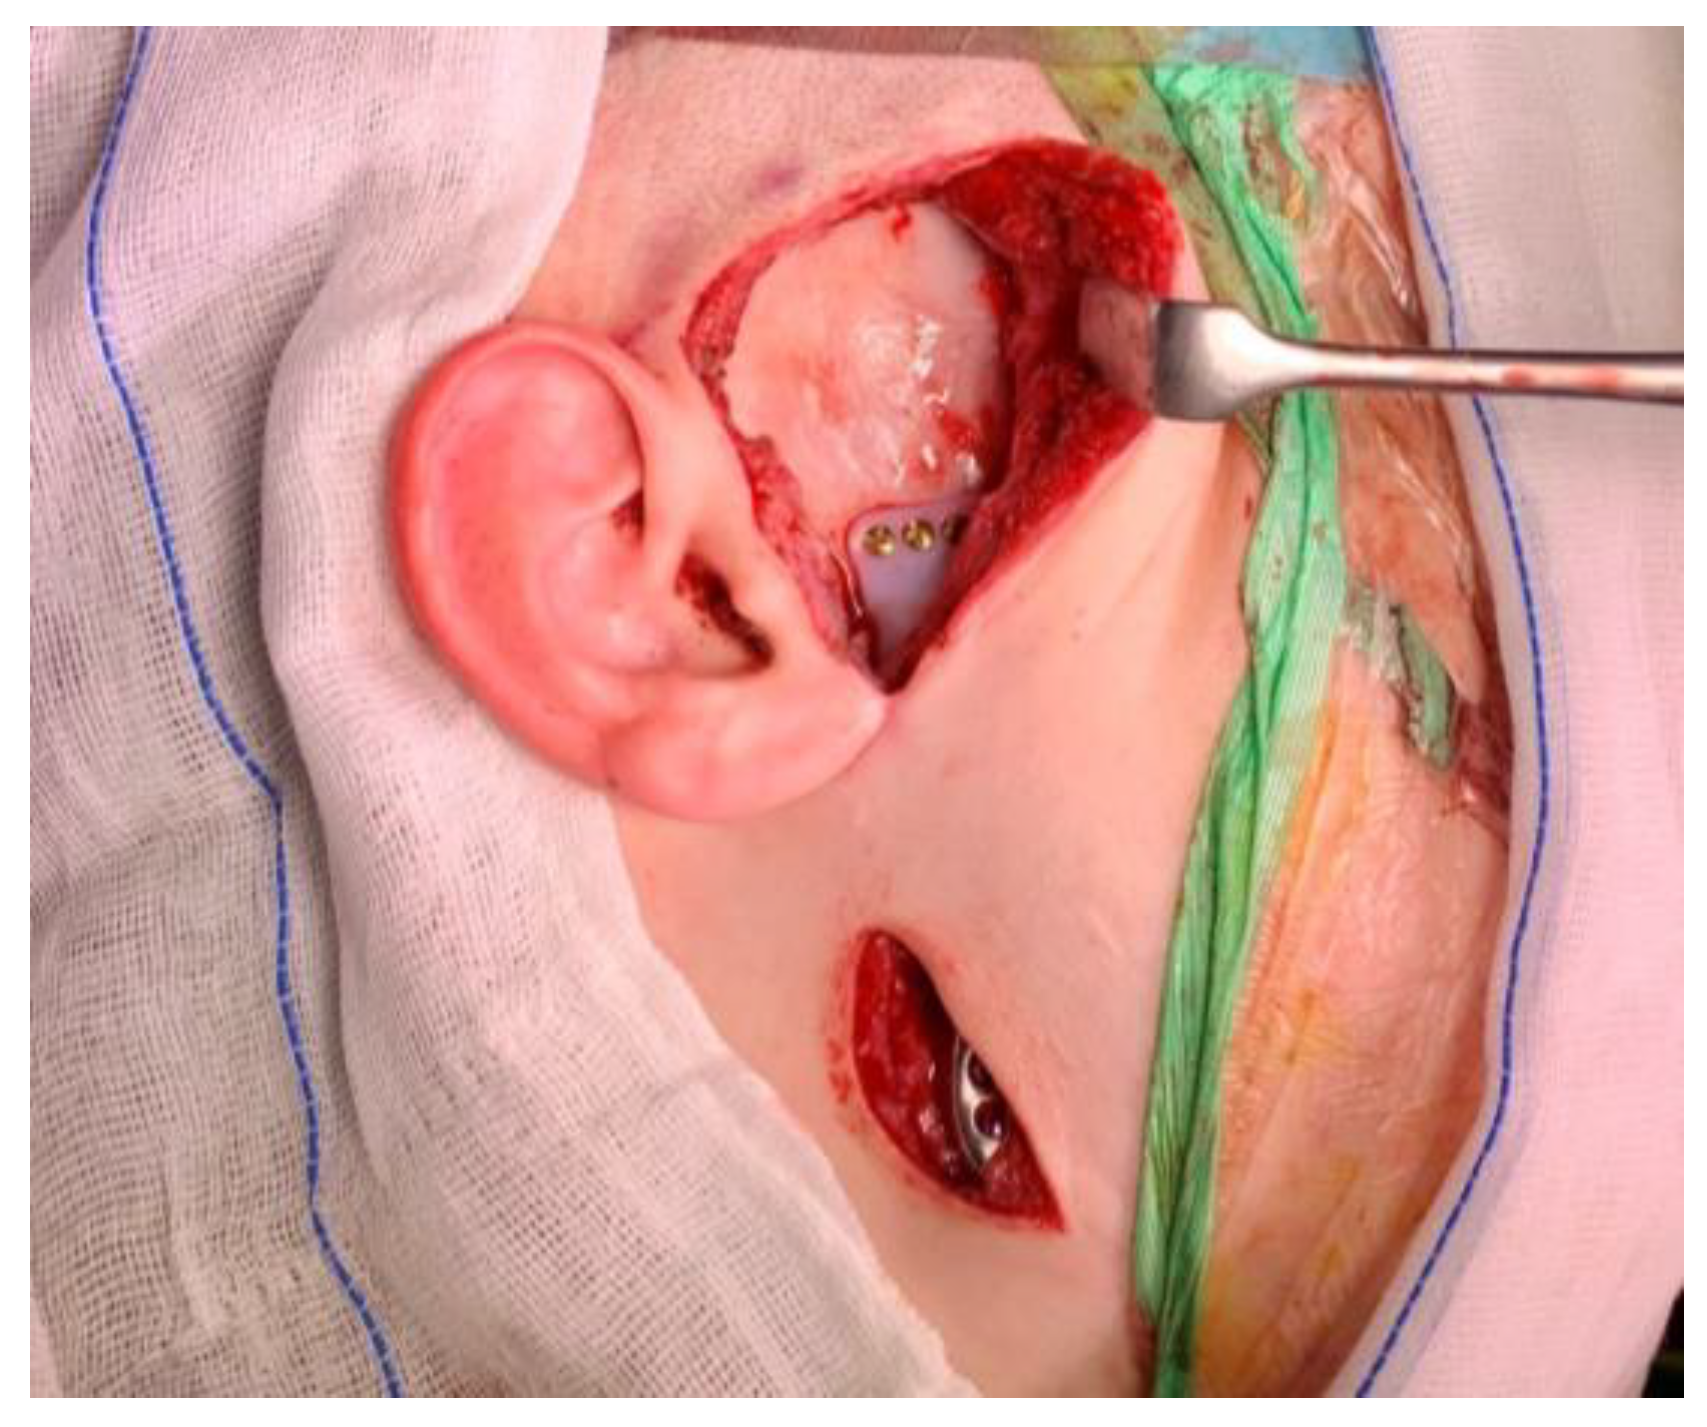

2.3. Surgical Technique

2.3.1. Mandible